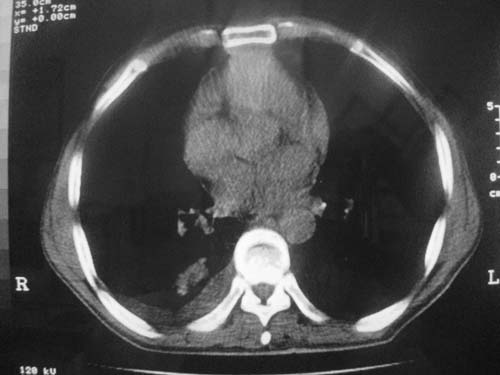

以下是引用科室第一人在2010-3-25 20:30:00的发言:[br]1:纵膈肿瘤性病变,恶性胸腺瘤可能性大伴纵膈右肺门淋巴结转移,右侧胸腔积液。[br]2:右侧肺门肿瘤性病变,纵膈淋巴结转移,右侧胸腔积液。右下叶转移。

以下是引用子期在2010-3-25 21:00:00的发言:[br]先考虑右中央型肺癌伴转移。

以下是引用江广1996在2010-3-25 22:49:00的发言:[br]通常肺癌向纵隔转移多见,纵隔肿瘤向肺内转移少见(有的表现为向肺内侵润)。本例以一元论考虑:右中心型肺癌并纵隔淋巴等多处转移。[br][br][本贴已被 江广1996 于 2010-3-25 22:50:07 修改过]

以下是引用yangyudong333在2010-3-26 6:43:00的发言:[br]“冰冻纵膈”,考虑纵膈淋巴瘤伴肺内及胸膜侵润。